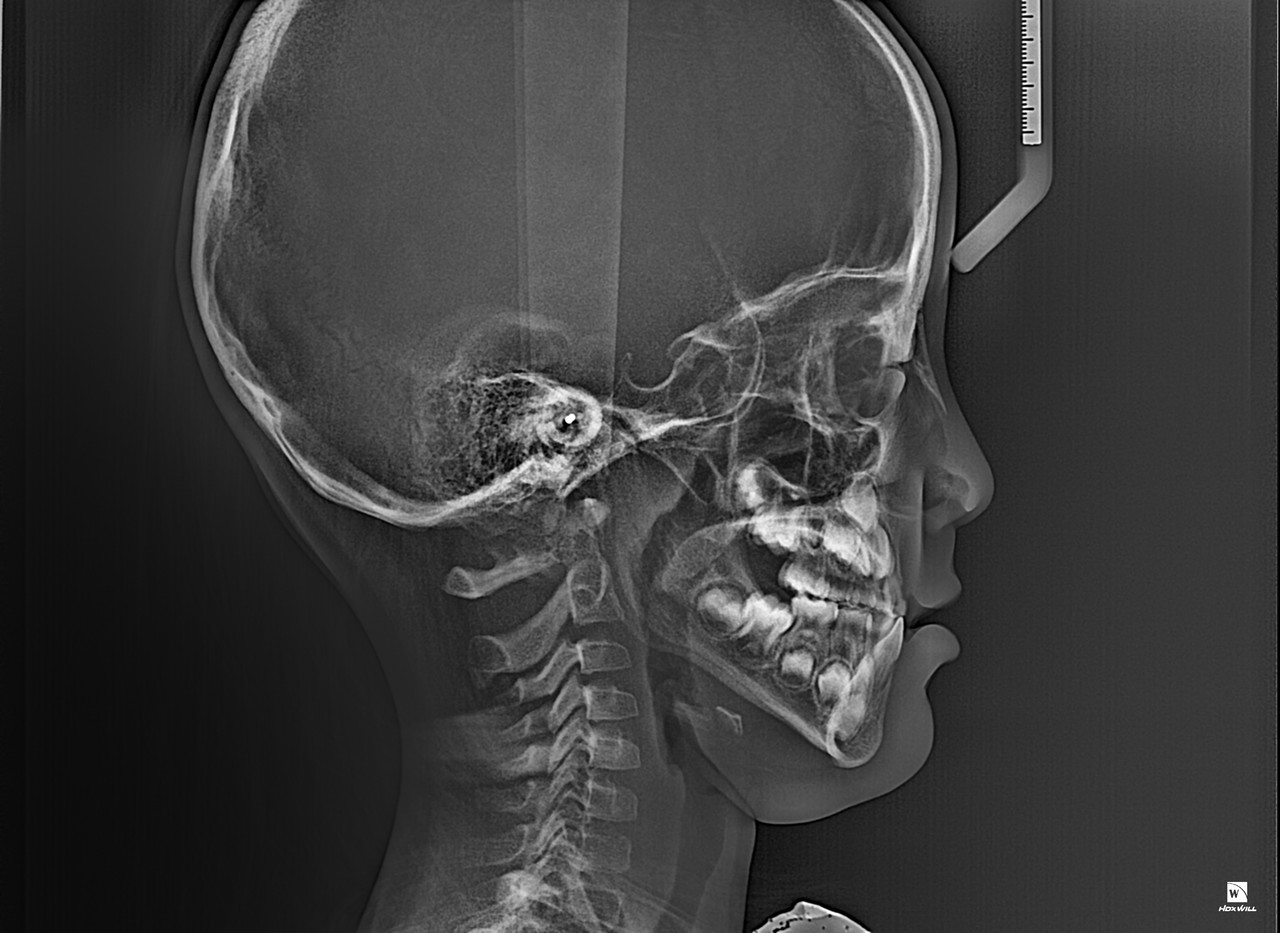

1차 교정(Phase I Orthodontic Treatment)은 혼합 치열기(유치와 영구치가 같이 있는 시기)

또는 초등학교 저학년~중학교 초반 정도의 어린 나이에 진행되는 초기 교정 치료입니다.

목표는 턱의 성장 조절, 심각한 부정교합 예방, 공간 확보, 습관 개선 등 입니다.

턱 성장 유도 및 조절

아래턱 또는 위턱이 지나치게 앞으로 나오거나 뒤로 들어간 경우, 성장기에 맞춰 유도

영구치가 날 공간 확보

유치가 너무 일찍 빠지거나, 공간이 부족해 영구치가 삐뚤게 날 것을 방지

심한 부정교합 예방

심한 반대교합(아래턱이 앞으로 나온 경우)이나 개방교합 등은 조기에 개입 필요

구강 습관 개선

손가락 빨기, 혀 내밀기, 구호흡 등 나쁜 습관으로 인한 부정교합 예방

대부분의 경우 1차 교정 후에도 영구치가 모두 나고 나서 2차 교정(본격적인 전체 교정)이 필요합니다.

1차 교정은 문제를 미리 완화하고, 이후 교정을 더 효율적이고 짧게 만들기 위한 예방적 치료로 볼 수 있습니다.